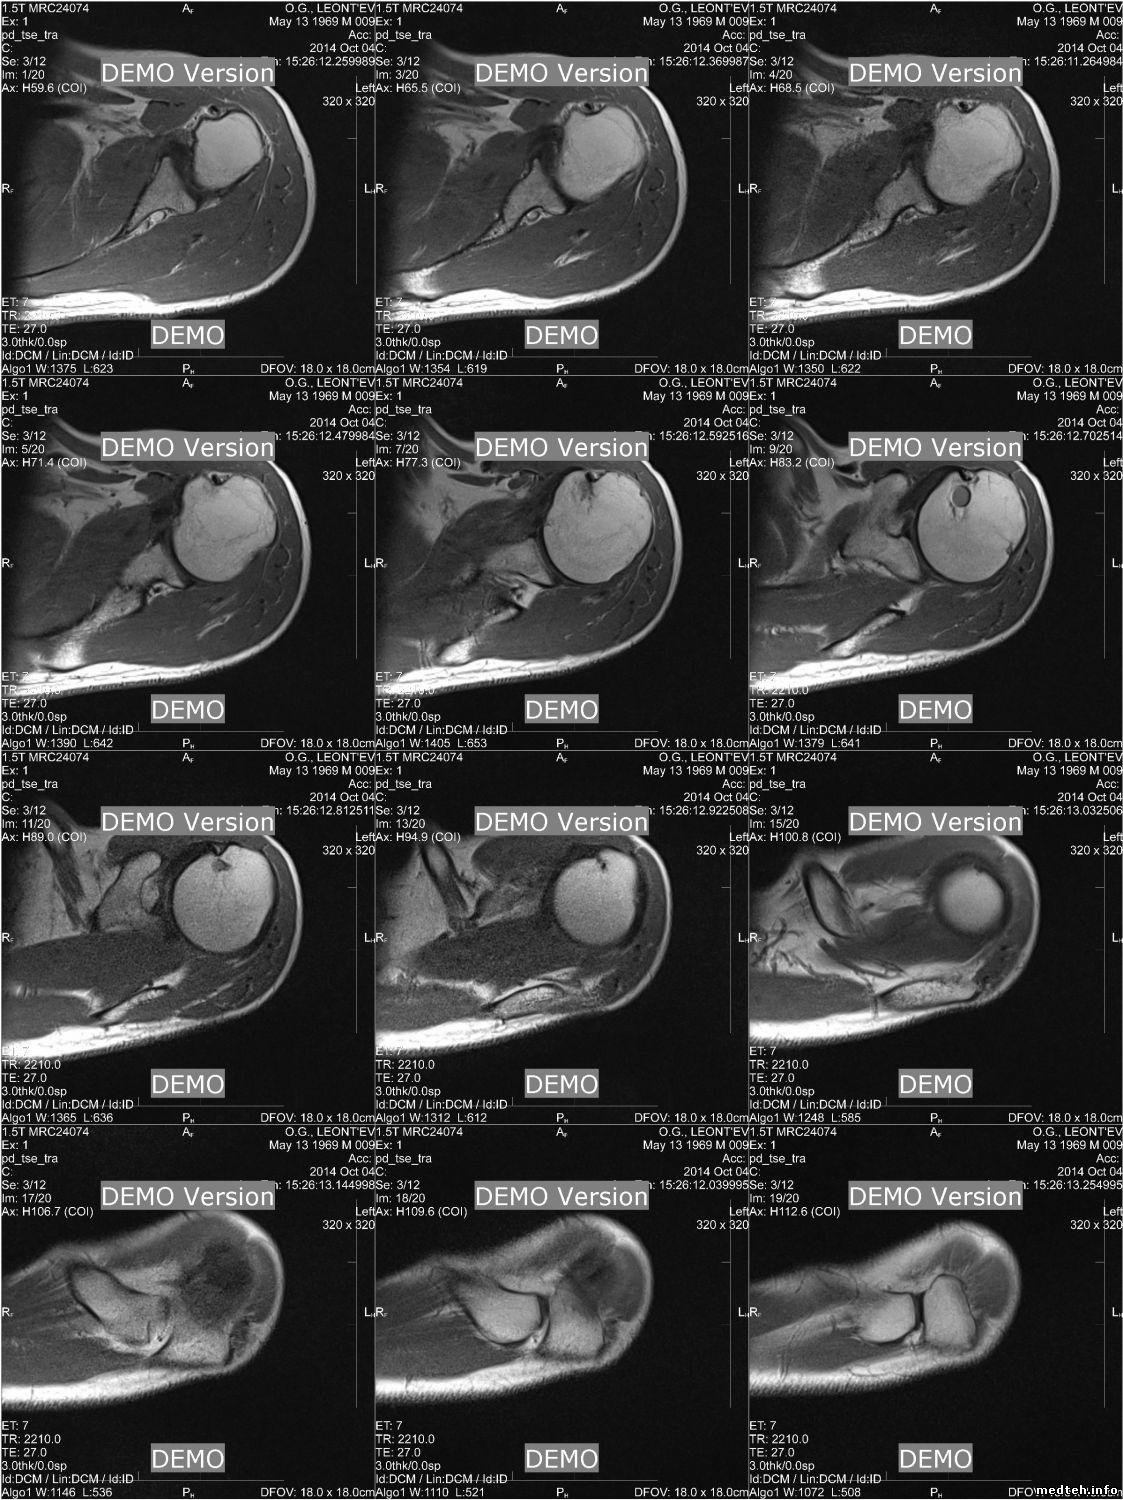

Как я понял вам вот что нужно, не сочтите за рекламу

http://charruasoft.com/products/printscp/index.php

В данном примере печать на эмулятор ДИСОМ принтер из eFima (что бы смакетировать DICOM print), в pdf что б даже бумагу не использовать :-)

прога платная :-(, есть заброшенный свой проект эмулятора DICOMprint, но получается все же дороже чем купить.

PrintSCP умеет в JPEG складывать

5144934.jpg (268.0 Kb)